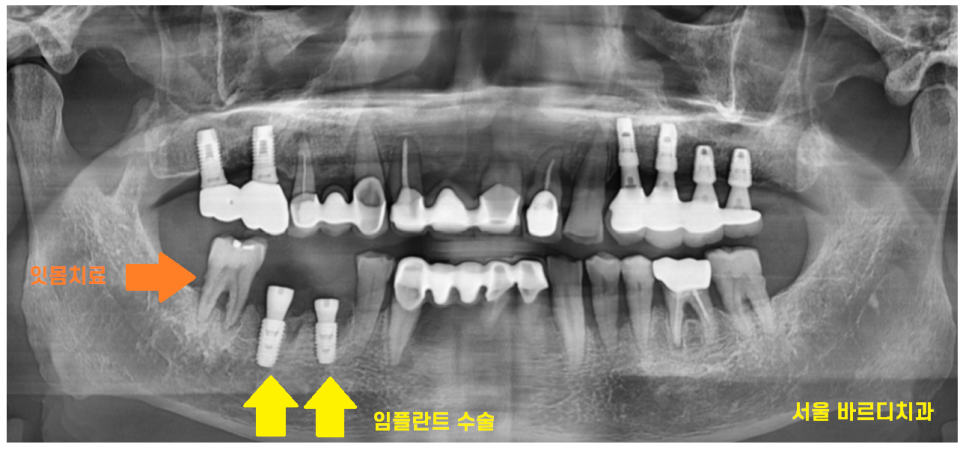

일반적으로는 아래 어금니는 3개월 뒤에

머리를 완성해드리지만

치아 욱신거림의 원인이

잇몸 이었던만큼

5개월정도

충분히 기다린 후 보철을 만들었습니다 .

23.11.02

23.11.09

치료 후 잇몸 염증이 많이 사라지긴 했지만

한번 내려간 잇몸의 경우

회복이 어렵습니다.

정기적으로 하남시청치과에 방문하셔서

임플란트와 잇몸

두가지 모두 관리하시기로 약속하셨답니다~